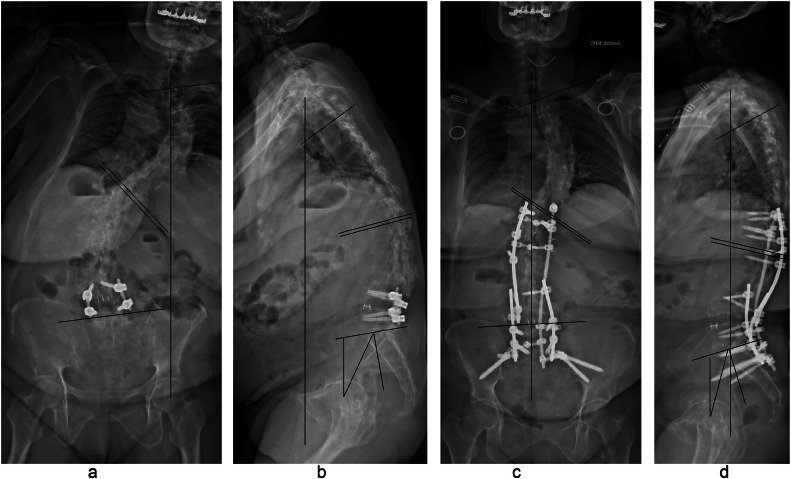

Fig. 8.

Fifty-two y old patient with previous L4L5 fusion. Preoperative full spine anteroposterior and lateral X-ray showing thoracolumbar kyphosis leading to sagittal malalignment associated to coronal malalignment (a and b), C7-CSVL>10 cm, lumbar coronal Cobb=55°, thoracic coronal cobb=53°, PI=34°, PT=27°, SVA>10 cm, LL=+5°, TK=21° Postoperative full spine anteroposterior and lateral X-ray after L4 PSO demonstrating significant improvement of the patient's alignment in both planes, multiple iliac screws and rods were used for stronger construct (C and D), C7-CSVL=0.5 cm, lumbar coronal Cobb=38°, thoracic coronal Cobb=54°, PI=34°, PT=15°, SVA=1.5 cm, LL=−30°, TK=39°.